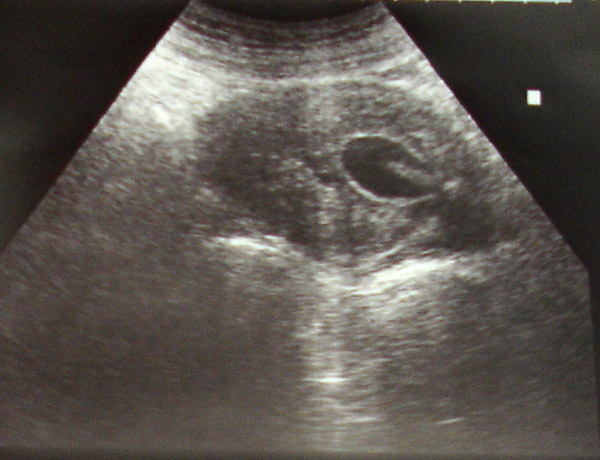

ECO cálculos en vías biliares